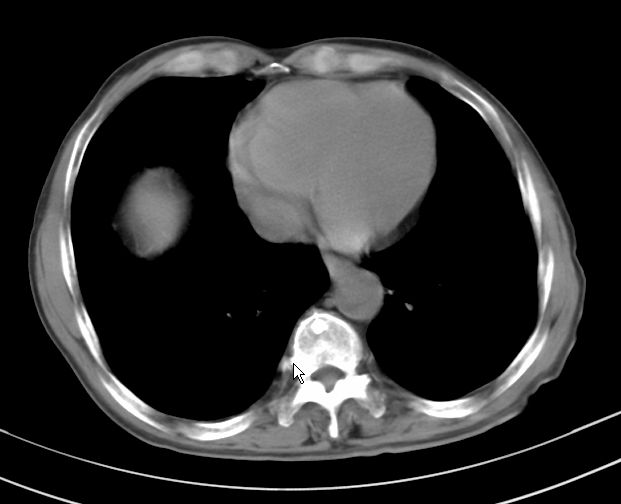

支持右肺上叶前段\\下叶内基底段感染,建议抗炎治疗后复查,除外结核.

支持右肺上叶前段、下叶内基底段感染,建议抗炎治疗后复查,除外结核.

右肺上叶前段及下叶内基底段感染性病变;建议抗炎治疗后复查。

楼主说是炎症,凭啥?典型的周围型肺癌(腺癌可能性大),肝内可能已有转移,强化看看吧。